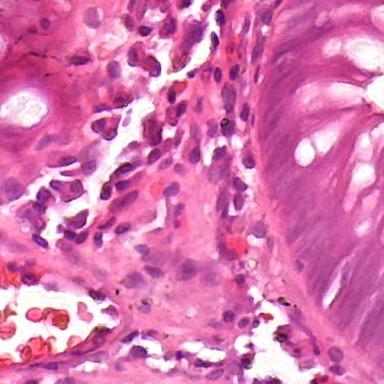

In this work, I propose a supervised deep learning-based model for accurate automatic cell nuclei segmentation. Given a tissue image, it begins with a deep convolutional neural network model to generate a probability map. Next, a threshold and morphological operations are applied to distinguish the background and the cells.

One of the significant benefits of the proposed method is that it can be applicable to different staining histopathology images taken of different patients. Due to the feature learning characteristic of deep convolutional neural network and the high level shape prior modeling, the proposed method is general enough to work properly across different image scenario like healthy, adenoma, hyperplasia.

Finally, I validated the proposed algorithm on several histopathology images using a range of different tissue from various patients with differents diseases.